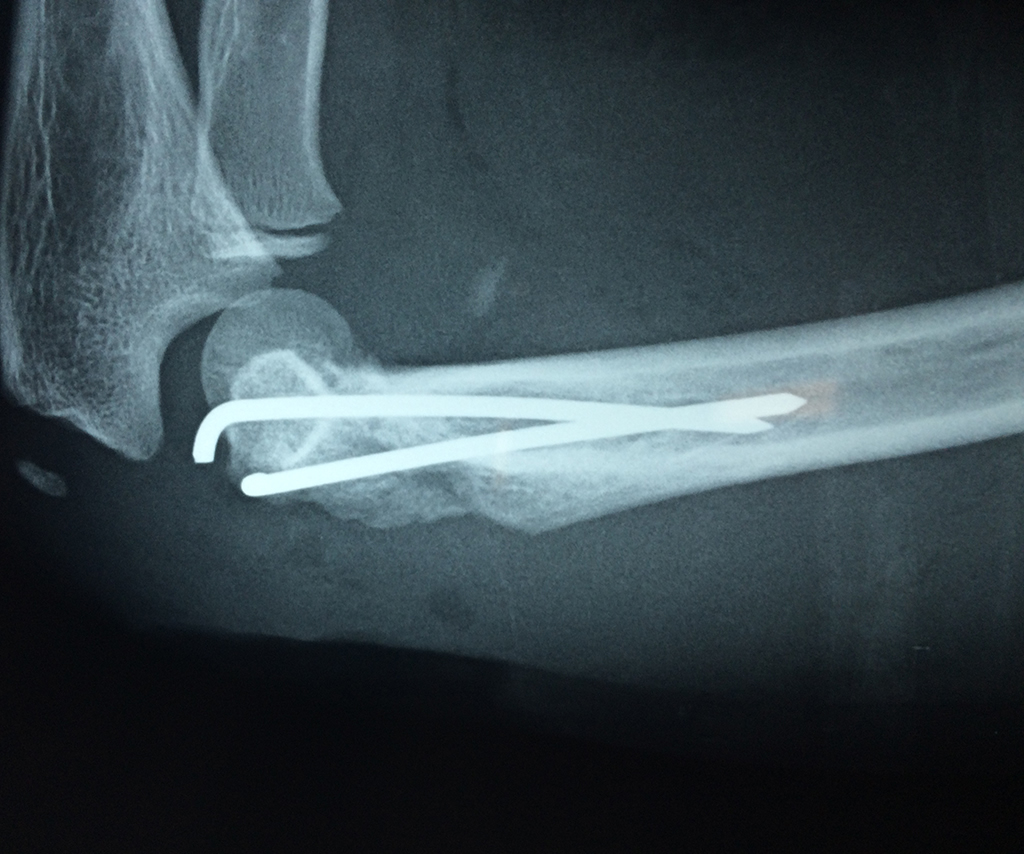

Cirugías de Húmero - Codo

En anatomía humana, la articulación del codo es la que une el brazo con el antebrazo, conectando la parte distal del hueso húmero con los extremos proximales de los huesos cúbito y radio.

Por otra parte el cúbito y el radio forman también una articulación entre si en las proximidades del codo, la cual se denomina articulación radio-cubital proximal.